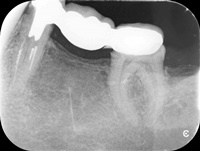

Przed trzema laty ząb 16 (prawa górna szóstka) był przeleczony endodontycznie i wykonano most. W ciągu 18 miesięcy od osadzenia mostu pacjentce kilka razy formował sie ropień dziąsła, osiem razy podawano antybiotyki. Gdy to nie pomagało, wykonano resekcję policzkowego korzenia zęba 16. Nie pomogło. W dalszym ciągu dochodziło do stanów zapalnych i antybiotykoterapii. W tym stanie pacjentka zgłosiła się, do naszego gabinetu. Zdjęto most, przeprowadzono ponowne leczenie kanałowe. Po sześciu miesiącach wykonano nowy most. Upłynęło półtora roku. Nie dochodzi do nawrotów stanu zapalnego, ani obrzęków. Ten przypadek pokazuje, dlaczego tak ważne jest poprawnie wykonane leczenie kanałowe, według nowoczesnego protokołu leczenia.